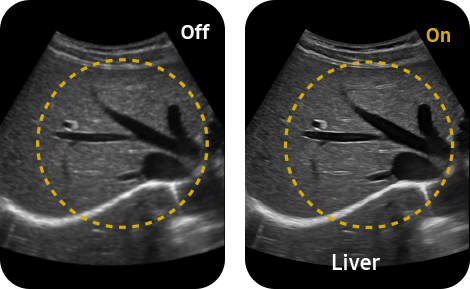

in shadowed regions

ShadowHDR™ selectively applies high-frequency and low-frequency of ultrasound to identify shadow areas where attenuation occurs.